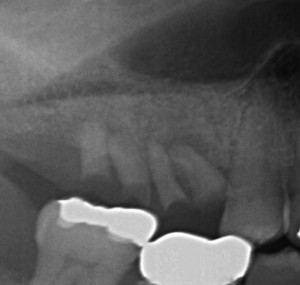

ここまで来ると痛くないですが、神経が腐って、骨が溶け出す病気がスタートします。(怖いですよね?)

で、最後は・・・

PBN334_141126191048(調整後)

ここまで来ると、残せません。